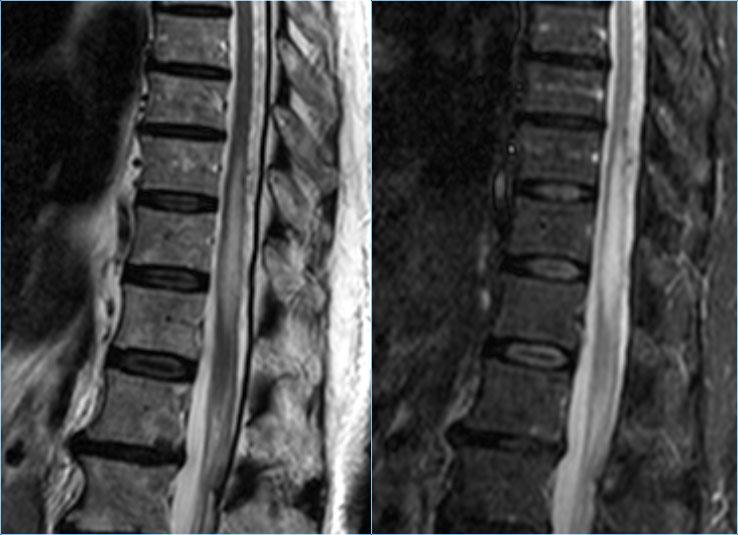

Đây là hình ảnh của một trường hợp điển hình.

Nhiều khi tiền sử lâm sàng rất hữu ích như trong trường hợp này.

Bệnh nhân nữ 24 tuổi có rối loạn thị giác một mắt, sau đó vài năm xuất hiện yếu và rối loạn cảm giác ở chi dưới và chi trên.

Hiện tại bệnh nhân đến khám vì rối loạn cảm giác ở cả hai chi dưới.

Vì vậy chúng ta đã nghĩ đến MS.

Trong tủy sống có một số tổn thương bờ rõ, nhưng cũng có một số tổn thương bờ không rõ, mờ nhạt.

Hình ảnh cắt ngang cho thấy vị trí ở phía lưng và hình dạng tam giác điển hình.

Tiếp tục xem các hình ảnh sau tiêm thuốc tương phản từ

Trên các hình ảnh sau tiêm thuốc tương phản từ, không thấy ngấm thuốc.

Các tổn thương MS hoạt động ở tủy sống có thể ngấm thuốc, nhưng không phổ biến như các tổn thương hoạt động ở não.

Khi phát hiện tổn thương ở tủy sống, việc chụp thêm não cũng rất hữu ích.

Đôi khi bệnh nhân chỉ được chỉ định chụp MRI cột sống và không có đủ thời gian để thực hiện toàn bộ khảo sát não.

Trong những trường hợp đó, hãy cân nhắc chỉ thực hiện chuỗi xung FLAIR mặt phẳng đứng dọc.

Tiếp tục xem các hình ảnh của não.

MRI não cho thấy các tổn thương quanh não thất và một tổn thương ở thể chai.

Các vị trí này rất đặc trưng cho MS.

Ở một bệnh nhân khác có các tổn thương không đặc hiệu trong tủy sống.

Chỉ dựa vào khảo sát cột sống đơn thuần, chúng ta có một chẩn đoán phân biệt rộng.

Tuy nhiên khi khảo sát thêm não, sẽ rõ ràng rằng chúng ta đang đối mặt với MS.

Trong trường hợp này, các hình ảnh trên não rất hữu ích.

Vị trí của các tổn thương rất điển hình: cầu não, quanh não thất và dưới vỏ não.